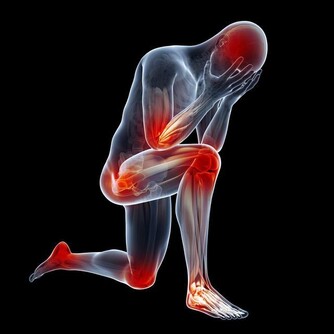

二、誘發心腦血管疾病

熬夜時人處於緊張狀態,得不到放鬆,造成血管收縮異常,血壓比正常人高,容易誘發高血壓或者加重病情。現在心腦血管疾病發病率逐漸增多且越來越年輕化,常熬夜或是誘因之一。